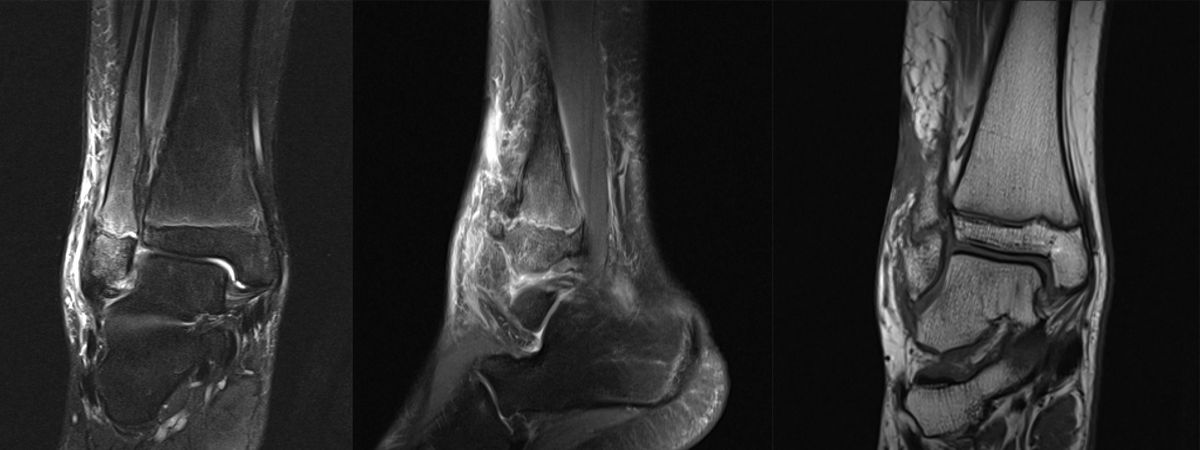

MRT

Die Kernspintomographie hat ihre Stärke in der Darstellung von Weichteilverletzungen. Insbesondere Verletzungen der Wachstumsfuge, des Periosts und der Bänder lassen sich gut visualisieren. Nachteilig ist die Untersuchungsdauer von 20-30 Minuten. Bleibt das Kind während dieser Zeit nicht ruhig liegen, kommt es zu Bewegungsartefakten, welche die Beurteilbarkeit der Bilder beeinträchtigen.

Fugengelenkfrakturen treten typischerweise vor dem 10. Lebensjahr auf, in einer Phase, in welcher die Wachstumsfugen noch weit offen sind. Dieser Frakturtyp betrifft fast ausschließlich den medialen Malleolus. Laterale Frakturen sind extrem selten, teilweise kommt es zu lateralen Bandverletzungen oder Fugenschaftfrakturen der distalen Fibula. Die Frakturlinie verläuft in einer Verlängerungslinie von der medialen Taluskante nach proximal. Häufig stellen sich Verletzungen des Innenknöchels im Röntgenbild schlechter dar, insbesondere wenn die Aufnahmen verdreht sind oder die Ebene der Fraktur bei geringer Dislokation verkippt zur Röntgenebene liegt. Besteht klinisch der geringste Hinweis auf eine Verletzung des Innenknöchels, muss aufgrund der Tragweite der Verletzung durch entsprechende Aufnahmen gegebenenfalls auch Schnittbildverfahren die Verletzung sicher diagnostiziert oder ausgeschlossen werden (Abb. 15).